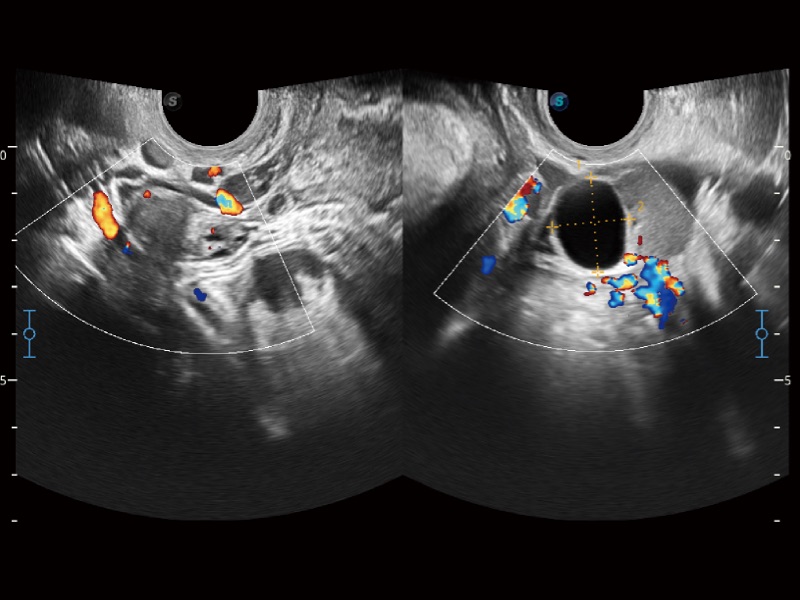

• SR Flow 高分辨率血流成像技术

高分辨率血流成像技术提高了对低速血流信号的检测能力。在提高空间分辨率的同时,也克服了血流外溢现象,为用户提供更加真实的血流动力学信息。

• 妇产科应用